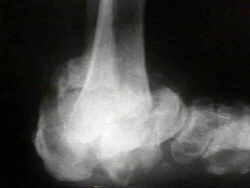

Refer to this picture for question 1. |

1. The following can precipitate or result from the condition shown in

the picture above: